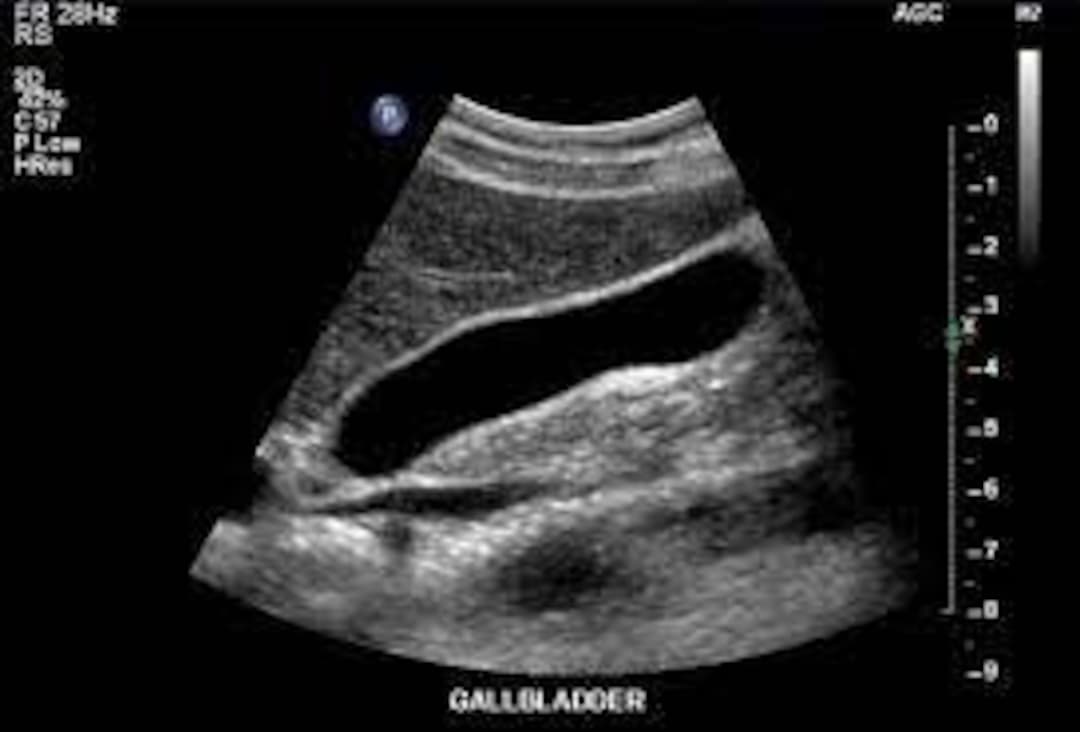

Renal cysts in Ferrets Vetlexicon

Renal cyst ultrasound 02 in Ferrets Vetlexicon Ferret Ultrasound The ferret was tachypneic, painful, dehydrated, pale, and obtunded on physical examination. Abdominal survey radiographs were available for eight ferrets and ultrasound examination for all cases. Ultrasound images from a ferret with lymphoma demonstrating infiltrative disease in the spleen (a) and liver (b). A definitive diagnosis is made via. Ultrasound may detect changes in size and consistency of the liver. Ferret Ultrasound.